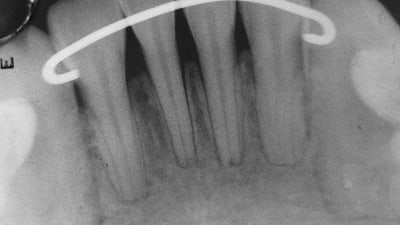

Online Only Online Only Peripheral Odontogenic Fibroma Associated with a Dilacerated Maxillary Central Incisor: A Case Report By Srinivas Sulugodu Ramachandra, BDSMDS, Umesh Chandra Prasad, MDS, Vidya Baliga, MDS October 01, 2011 8 min read